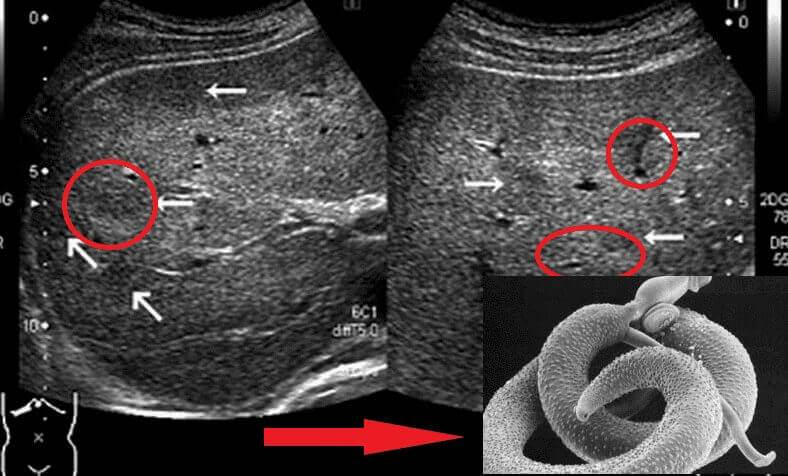

รูของพยาธิ ในลำไส้

พวกพยาธิที่เข้าทำลายอวัยวะสำคัญ ได้แก่ พยาธิตัวตืดหมู (Taenia solium), พยาธิตัวตืดหมา (Echinococcus granulosus), และพยาธิไตรคิเนลลา (Trichinella spiralis) โดยพยาธิตัวตืดหมาเป็นตัวอ่อนของพยาธิในสกุล Echinococcus และนี่เป็นเพียงส่วนหนึ่งของพยาธิหลายชนิดที่สามารถฆ่าคนได้